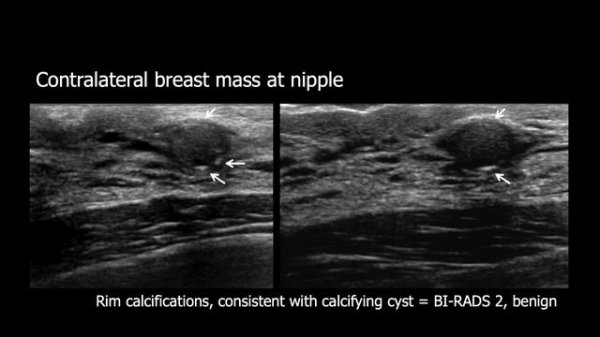

Improving Specificity of Breast Ultrasound: BI-RADS 3 and 4A

Как поймать РМЖ на ранней стадии? Скрининг рака молочной железы. Что такое BI RADS?

Mammography BI RADS МУСТАФИН ЧИНГИС